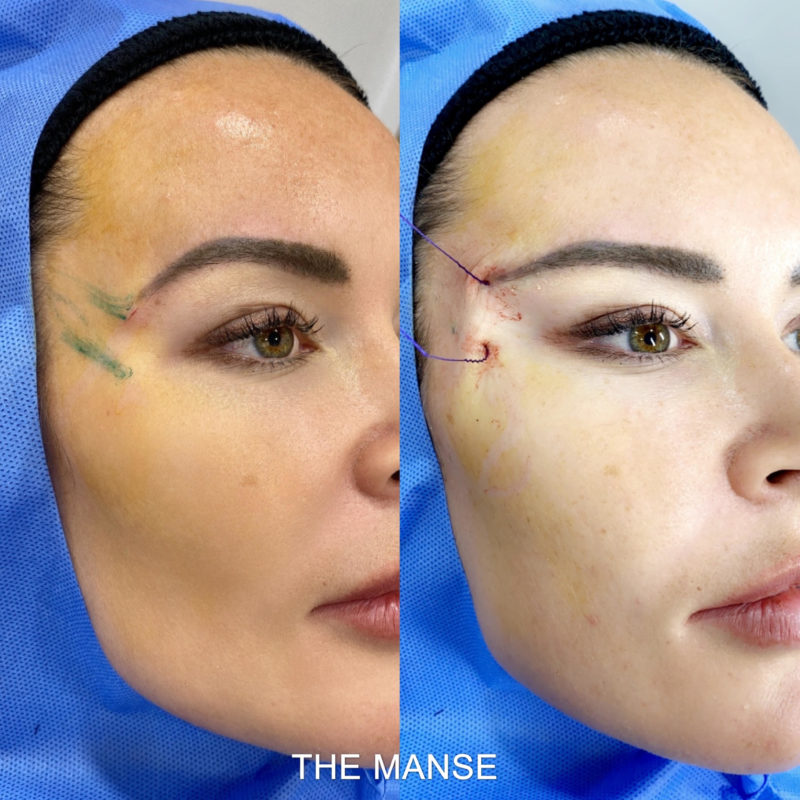

7. Canthoplasty

8. Lower eyelid retraction

7. Canthoplasty

8. Lower eyelid retraction